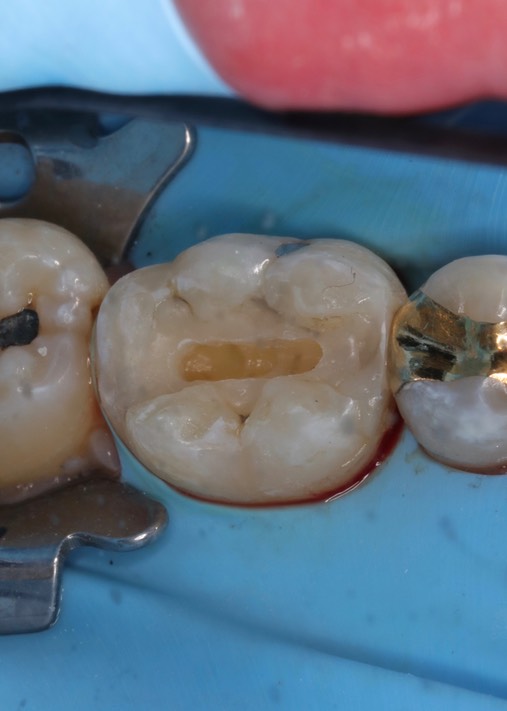

Kris Nip #30 composite buildup